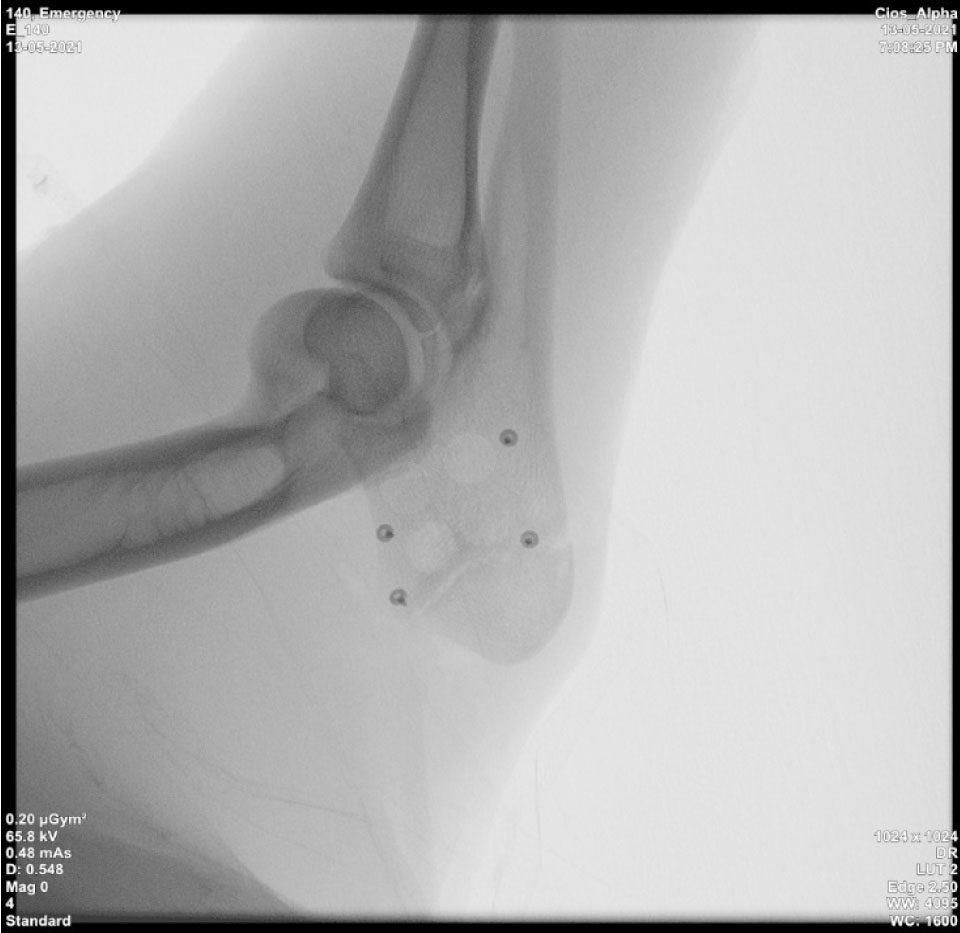

Рис. 1. Поперечный срез микротомографии локтевого отростка овцы

Учитывая выше перечисленные недостатки, поиск новых областей и способов хирургического доступа для создания экспериментальной модели исследования остеопластических материалов является актуальным. Нас заинтересовало использование в качестве экспериментальной живой модели область локтевого отростка передних конечностей овцы. В доступной литературе нами не встречено упоминаний об использовании локтевых отростков овец с целью формирования костных дефектов для оценки регенераторного потенциала остеопластических материалов. Вероятно, это обусловлено боязнью риска травматизма локтевого отростка в ходе формировании дефекта при использовании классического хирургического инструментария – сверл и фрез большого диаметра. Между тем очевиден ряд преимуществ данной области – схожее анатомическое строение и архитектоника с альвеолярной частью челюстей человека. Локтевой отросток имеет наружный кортикальный слой и внутренний, представленный губчатым веществом с костномозговыми пространствами небольшого размера (рис. 1, 2).